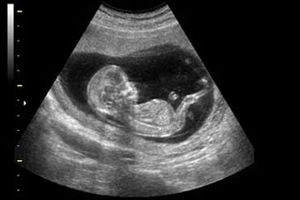

سونوگرافی برای جنین ضرر دارد؟

بسیاری از پزشکان نسبت به انجام سونوگرافیهای غیرضروری، تعدد آنها و صدمهای که این معاینهها میتوانند در ماههای مشخصی…